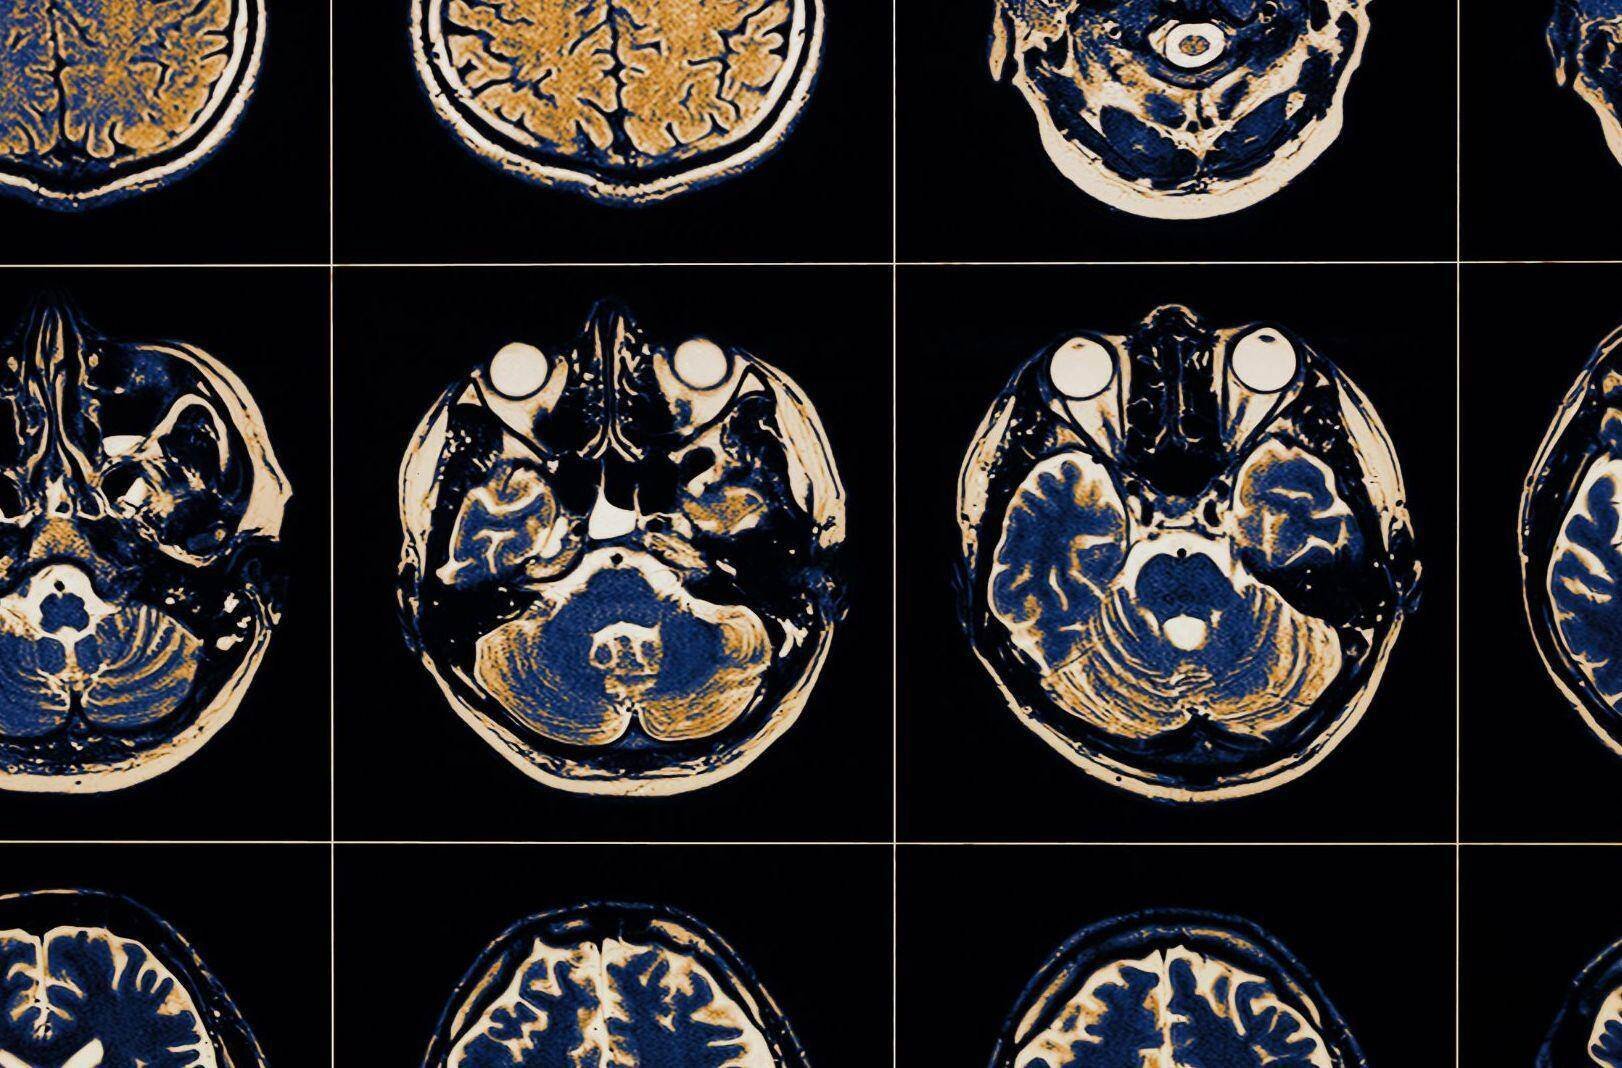

To evaluate persistent headaches, medical professionals might recommend diagnostic imaging tests such as X-rays or MRIs. These tests help to visualize the internal structures of the brain and skull, providing critical information that can guide the diagnosis and treatment. It is always recommended to closely monitor these symptoms and discuss them with a healthcare provider to rule out serious conditions and receive appropriate care.

Neurologists start with comprehensive physical examinations, gauging reflexes, coordination, muscle strength, and sensation. To accurately diagnose a patient, they may require diagnostic tests such as MRI or CT scans, which provide detailed images of the brain and spinal structures and help in identifying injuries like concussions, contusions, or more severe conditions.

- MRI (Magnetic Resonance Imaging): Provides detailed images of the brain and spinal cord.

- CT Scan (Computed Tomography): Helps detect bleeding and injuries quickly.